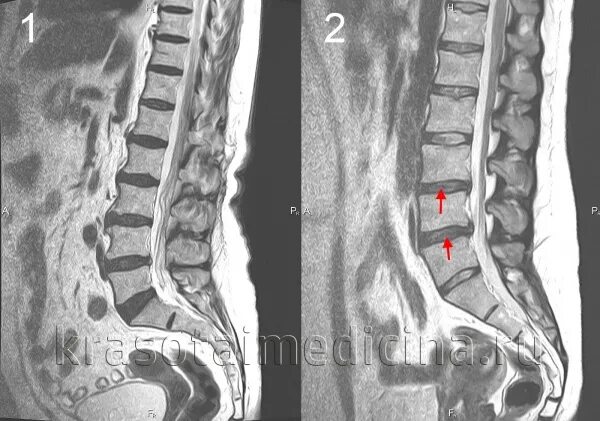

Дисков в сегменте l4 l5